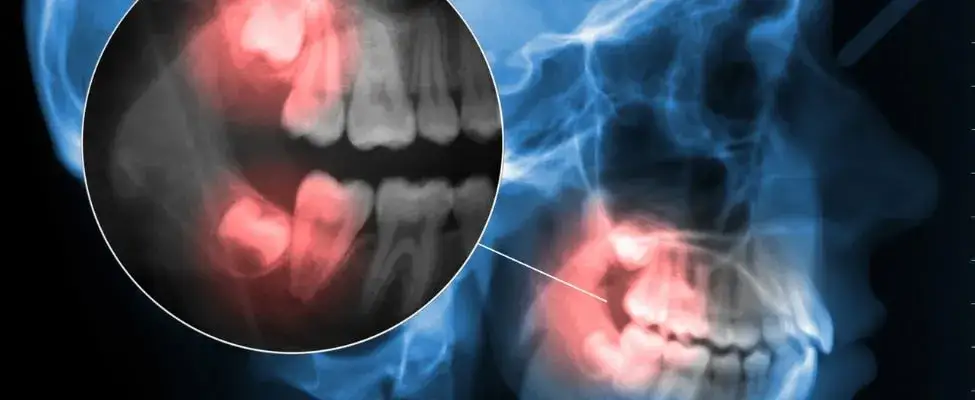

W dolnej szczęce ósemki mogą mieć większe problemy z miejscem, co często prowadzi do ich impakcji – stanu, w którym ząb nie może prawidłowo wyrastać. Warto zwrócić uwagę na to, że zęby mądrości w obu szczękach są zwykle zlokalizowane za drugimi zębami trzonowymi, co jest istotne przy planowaniu leczenia stomatologicznego.

Wzrost zębów mądrości, zwanych ósemkami, może wiązać się z różnymi problemami i komplikacjami. Jednym z najczęstszych problemów jest ból, który często występuje, gdy zęby te próbują przebić się przez dziąsła. W wielu przypadkach, ósemki mogą być zablokowane przez inne zęby, co prowadzi do ich impakcji. To zjawisko nie tylko powoduje dyskomfort, ale również może prowadzić do poważniejszych problemów, takich jak infekcje.

Wzrost zębów mądrości, znanych jako ósemki, może prowadzić do różnych komplikacji zdrowotnych. Jednym z najczęstszych problemów jest impakcja, czyli sytuacja, w której ząb nie ma wystarczająco miejsca, aby prawidłowo wyrastać. To może prowadzić do bólu, obrzęku oraz dyskomfortu w okolicy szczęki. Innym poważnym problemem jest uszkodzenie sąsiednich zębów, które mogą być wypychane lub przesuwane przez rosnącą ósemkę, co prowadzi do ich zniszczenia lub konieczności leczenia.

Dodatkowo, zęby mądrości mogą być źródłem infekcji, zwłaszcza jeśli częściowo przebiły się przez dziąsła. W takim przypadku bakterie mogą gromadzić się w obszarze wokół zęba, prowadząc do zapalenia i bólu. Warto również pamiętać, że problemy z zębami mądrości mogą wpływać na ogólny stan zdrowia jamy ustnej, co czyni regularne kontrole stomatologiczne niezwykle ważnymi.

- Impakcja: Ząb nie ma miejsca na prawidłowy wzrost, co prowadzi do bólu i dyskomfortu.

- Uszkodzenie sąsiednich zębów: Ósemki mogą przesuwać lub niszczyć inne zęby w jamie ustnej.

- Infekcje: Częściowe wyrastanie zęba mądrości może prowadzić do gromadzenia się bakterii i zapaleń.